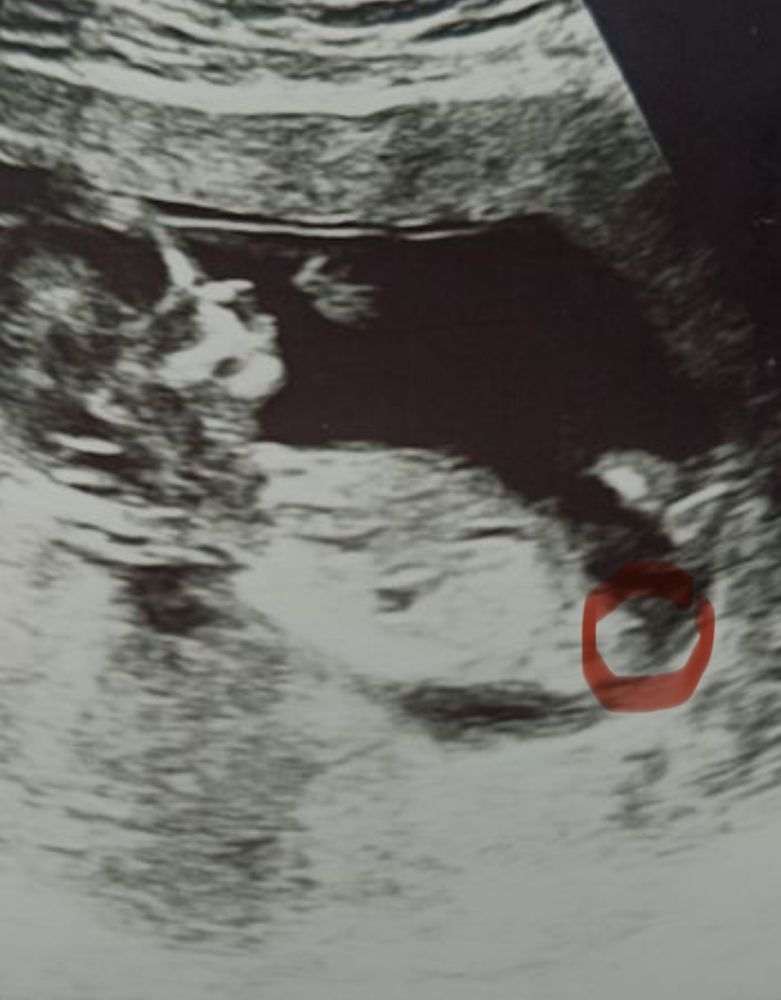

Марина, не могу понять, это половой бугорок?) Вы уже на опыте) Изображение

Светлана , нет это не подскажу, я гуглила сравнивала свое фото с интернетом, потом в итоге плюнула, думаю будет срок больше узнаю

Пол ребенка 16-17 недель 2 скрининг, узнали кого ждем 💙